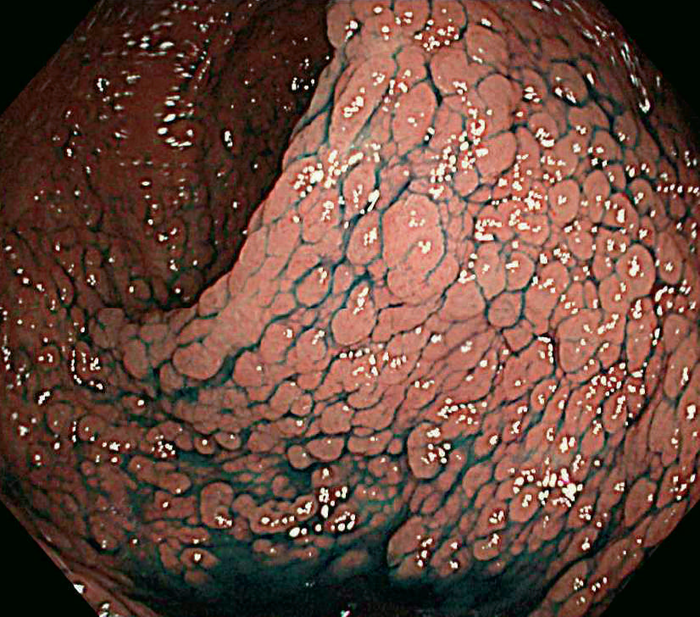

- 古典型FAPは数百から数千の大腸腺腫性ポリープを特徴とし,平均16歳(範囲7~36歳)から発症し始める。古典型FAPの場合,95%が35歳までにポリープを形成し,大腸切除などの介入を行わなければCRCは避けられない。未治療者のCRC診断の平均年齢は39歳(範囲34~43歳)である。古典型FAPは腺腫密度により,密生型FAP,非密生型FAPに分類されることがあり,肉眼的に正常粘膜が観察できないほど腺腫を発生し,腺腫数が>1,000個(または>2,000個)の場合,密生型FAP(severe/profuse/dense FAP)(図Ⅱ-1),正常粘膜を背景に腺腫が多発し腺腫数がおよそ100~1,000個(または2,000個)の場合,非密生型FAP(sparse FAP)と分類する(図Ⅱ-2)ことがある。ただし,大腸の部位によって腺腫密度が異なることもしばしば経験し,密生型と非密生型を厳密に区別する臨床的意義は乏しい。

図Ⅱ-1 密生型FAP